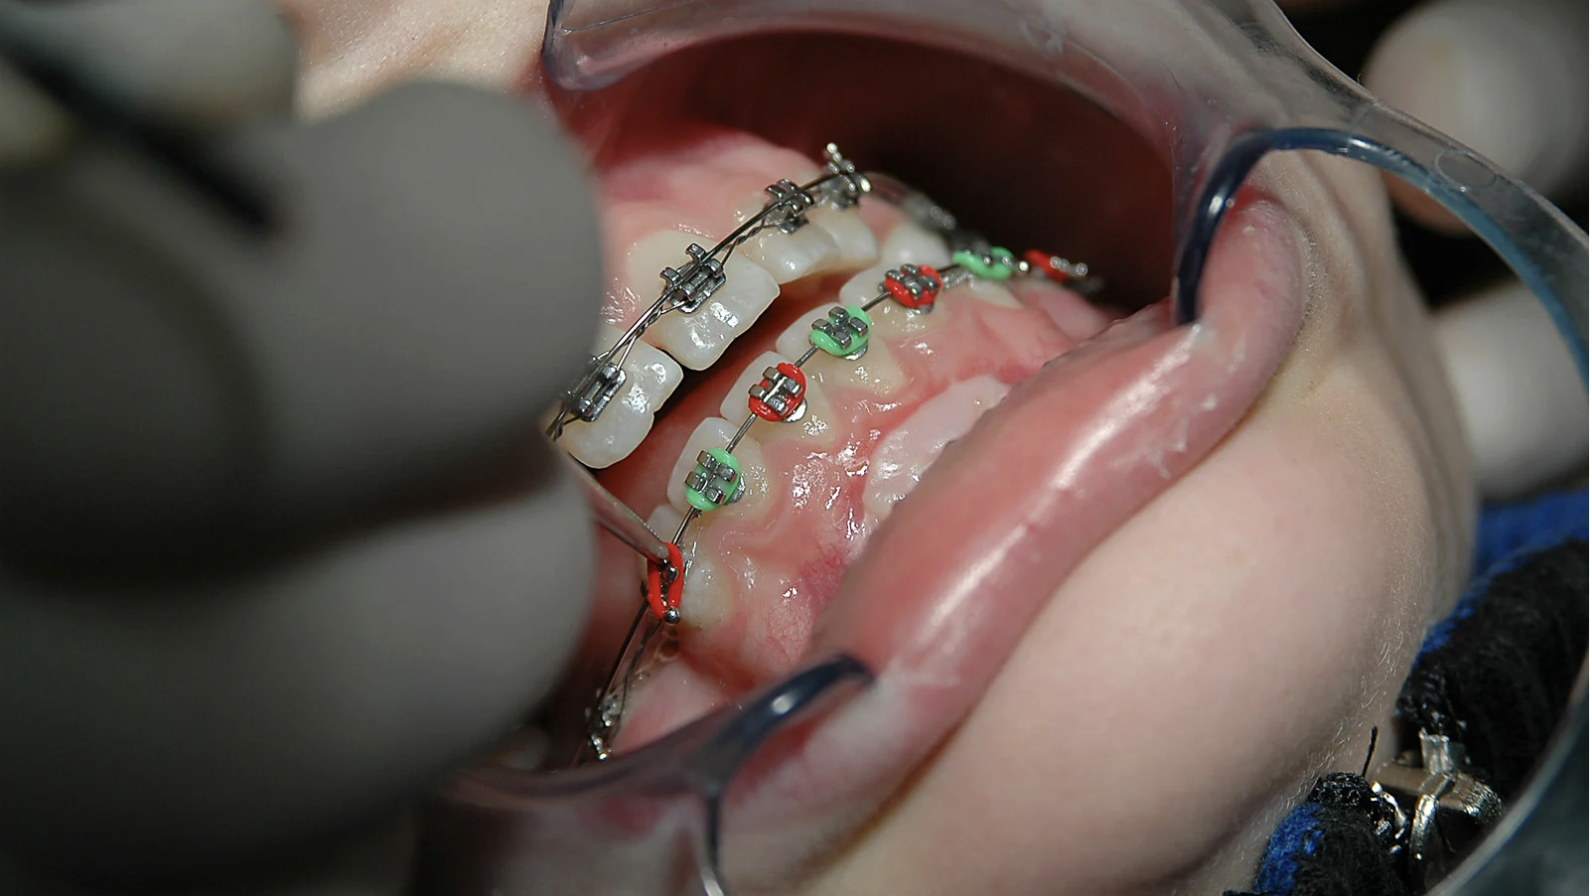

ただ、上下の小臼歯(前から4番目もしくは5番目の歯)を4本抜いて、ワイヤー矯正でしか治せないと診断され、歯を抜かずにマウスピース矯正で治療ができないかと、当院へお越しになられました。

・抜歯が必要な矯正治療はマウスピース矯正ではできないため、ワイヤー矯正が必要

下顎前歯のがたつきはやや大きい数値を示していましたが、抜歯をしたくないという患者様の強いご希望もあり、IPR(歯と歯の間をわずかに削る処置)、遠心移動(奥歯を後ろへ動かす)を

組み合わせてスペースを作成することで、

抜歯を行わずにマウスピース矯正で治療が可能と判断いたしました。

(奥歯を後ろに動かすため、親知らずの抜歯は行う)

また、ディープバイト改善のため、上下の前歯の圧下(顎の骨の中に埋め込む)を行い、適切な前歯の噛み合わせを作りました。